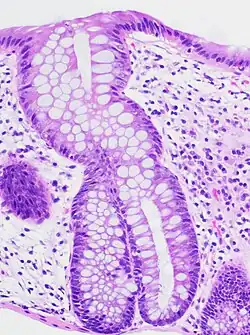

Micrograph of collagenous colitis. H&E stain.